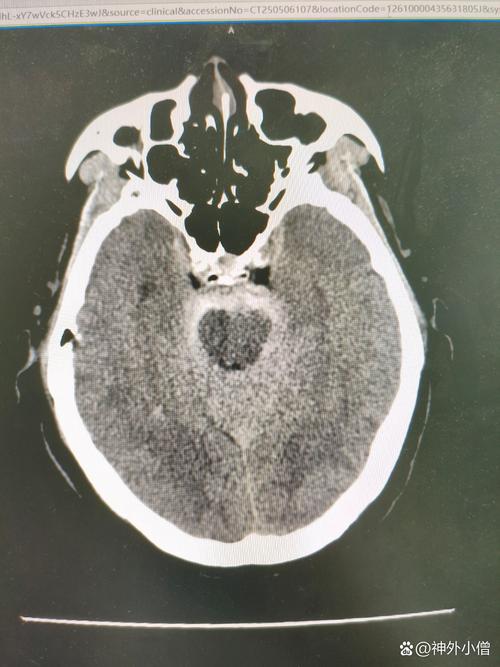

这是一个非常严重且复杂的情况,需要家属和医护人员高度警惕并紧密配合,我们来详细解析一下“脑梗脑疝术后肺部感染”的各个方面。

- 脑梗:大脑血管堵塞,导致脑组织缺血、缺氧、坏死,这本身就会影响全身,尤其是呼吸和循环中枢。

- 脑疝:这是脑梗最危险的并发症,由于颅内压力急剧增高,部分脑组织被挤入颅骨的天然孔道中,会压迫负责心跳、呼吸的脑干,是致死率极高的急症,需要立即手术。